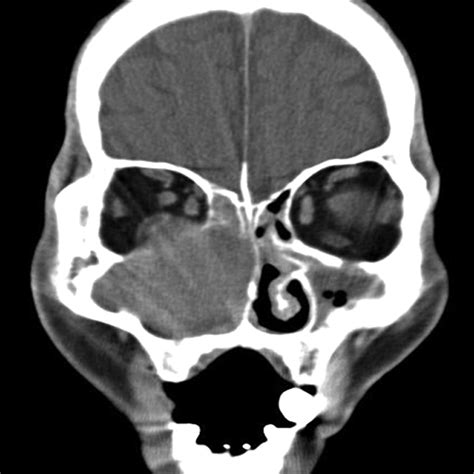

A Mxailliary Sinus CT scan, or Computed Tomography scan, is a non-invasive imaging procedure that uses X-rays to create detailed cross-sectional images of the sinuses. These images help doctors to identify abnormalities, infections, or structural issues within the sinuses. The scan is particularly useful for diagnosing conditions such as sinusitis, nasal polyps, and tumors.

The Mxailliary Sinus CT scan works by taking multiple X-ray images from different angles around the body. These images are then processed by a computer to create cross-sectional views of the sinuses. The resulting images provide a detailed view of the sinus cavities, allowing doctors to identify any abnormalities.

The results of a Mxailliary Sinus CT scan are interpreted by a radiologist, who will look for signs of:

• Inflammation: Swelling or infection in the sinuses.

• Obstruction: Blockages in the sinus passages.

• Abnormal Growths: Polyps, tumors, or other growths.

• Structural Issues: Deviated septum or other structural abnormalities.

Common Findings in a Mxailliary Sinus CT Scan

Some common findings in a Mxailliary Sinus CT scan include:

• Sinusitis: Inflammation of the sinuses, often due to infection.

• Nasal Polyps: Benign growths in the nasal passages.

• Tumors: Abnormal growths that may be benign or malignant.

• Fractures: Bone fractures in the sinus area, often due to trauma.

• Deviated Septum: A misaligned nasal septum that can cause obstruction.